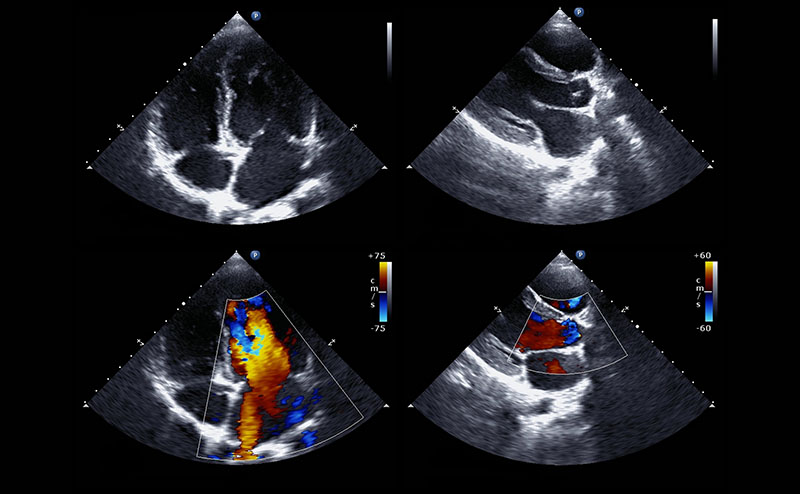

This clip displays cardiac tamponade with a large pericardial effusion. The effusion is causing diastolic collapse of the right ventricle and is concerning for tamponade physiology.

Chest: Respiratory distress with diffuse crackles

This video displays severe LV dilatation and systolic dysfunction with moderate inferior pericardial effusion. The patient ultimately was diagnosed with Anomalous Left Coronary Artery from the Pulmonary Artery (ALCAPA). In this process, the left coronary artery (LCA) arises from the pulmonary artery instead of the aorta, leading to a reversed blood flow and reduced oxygen supply to the heart muscle, causing ischemia and potentially heart failure.